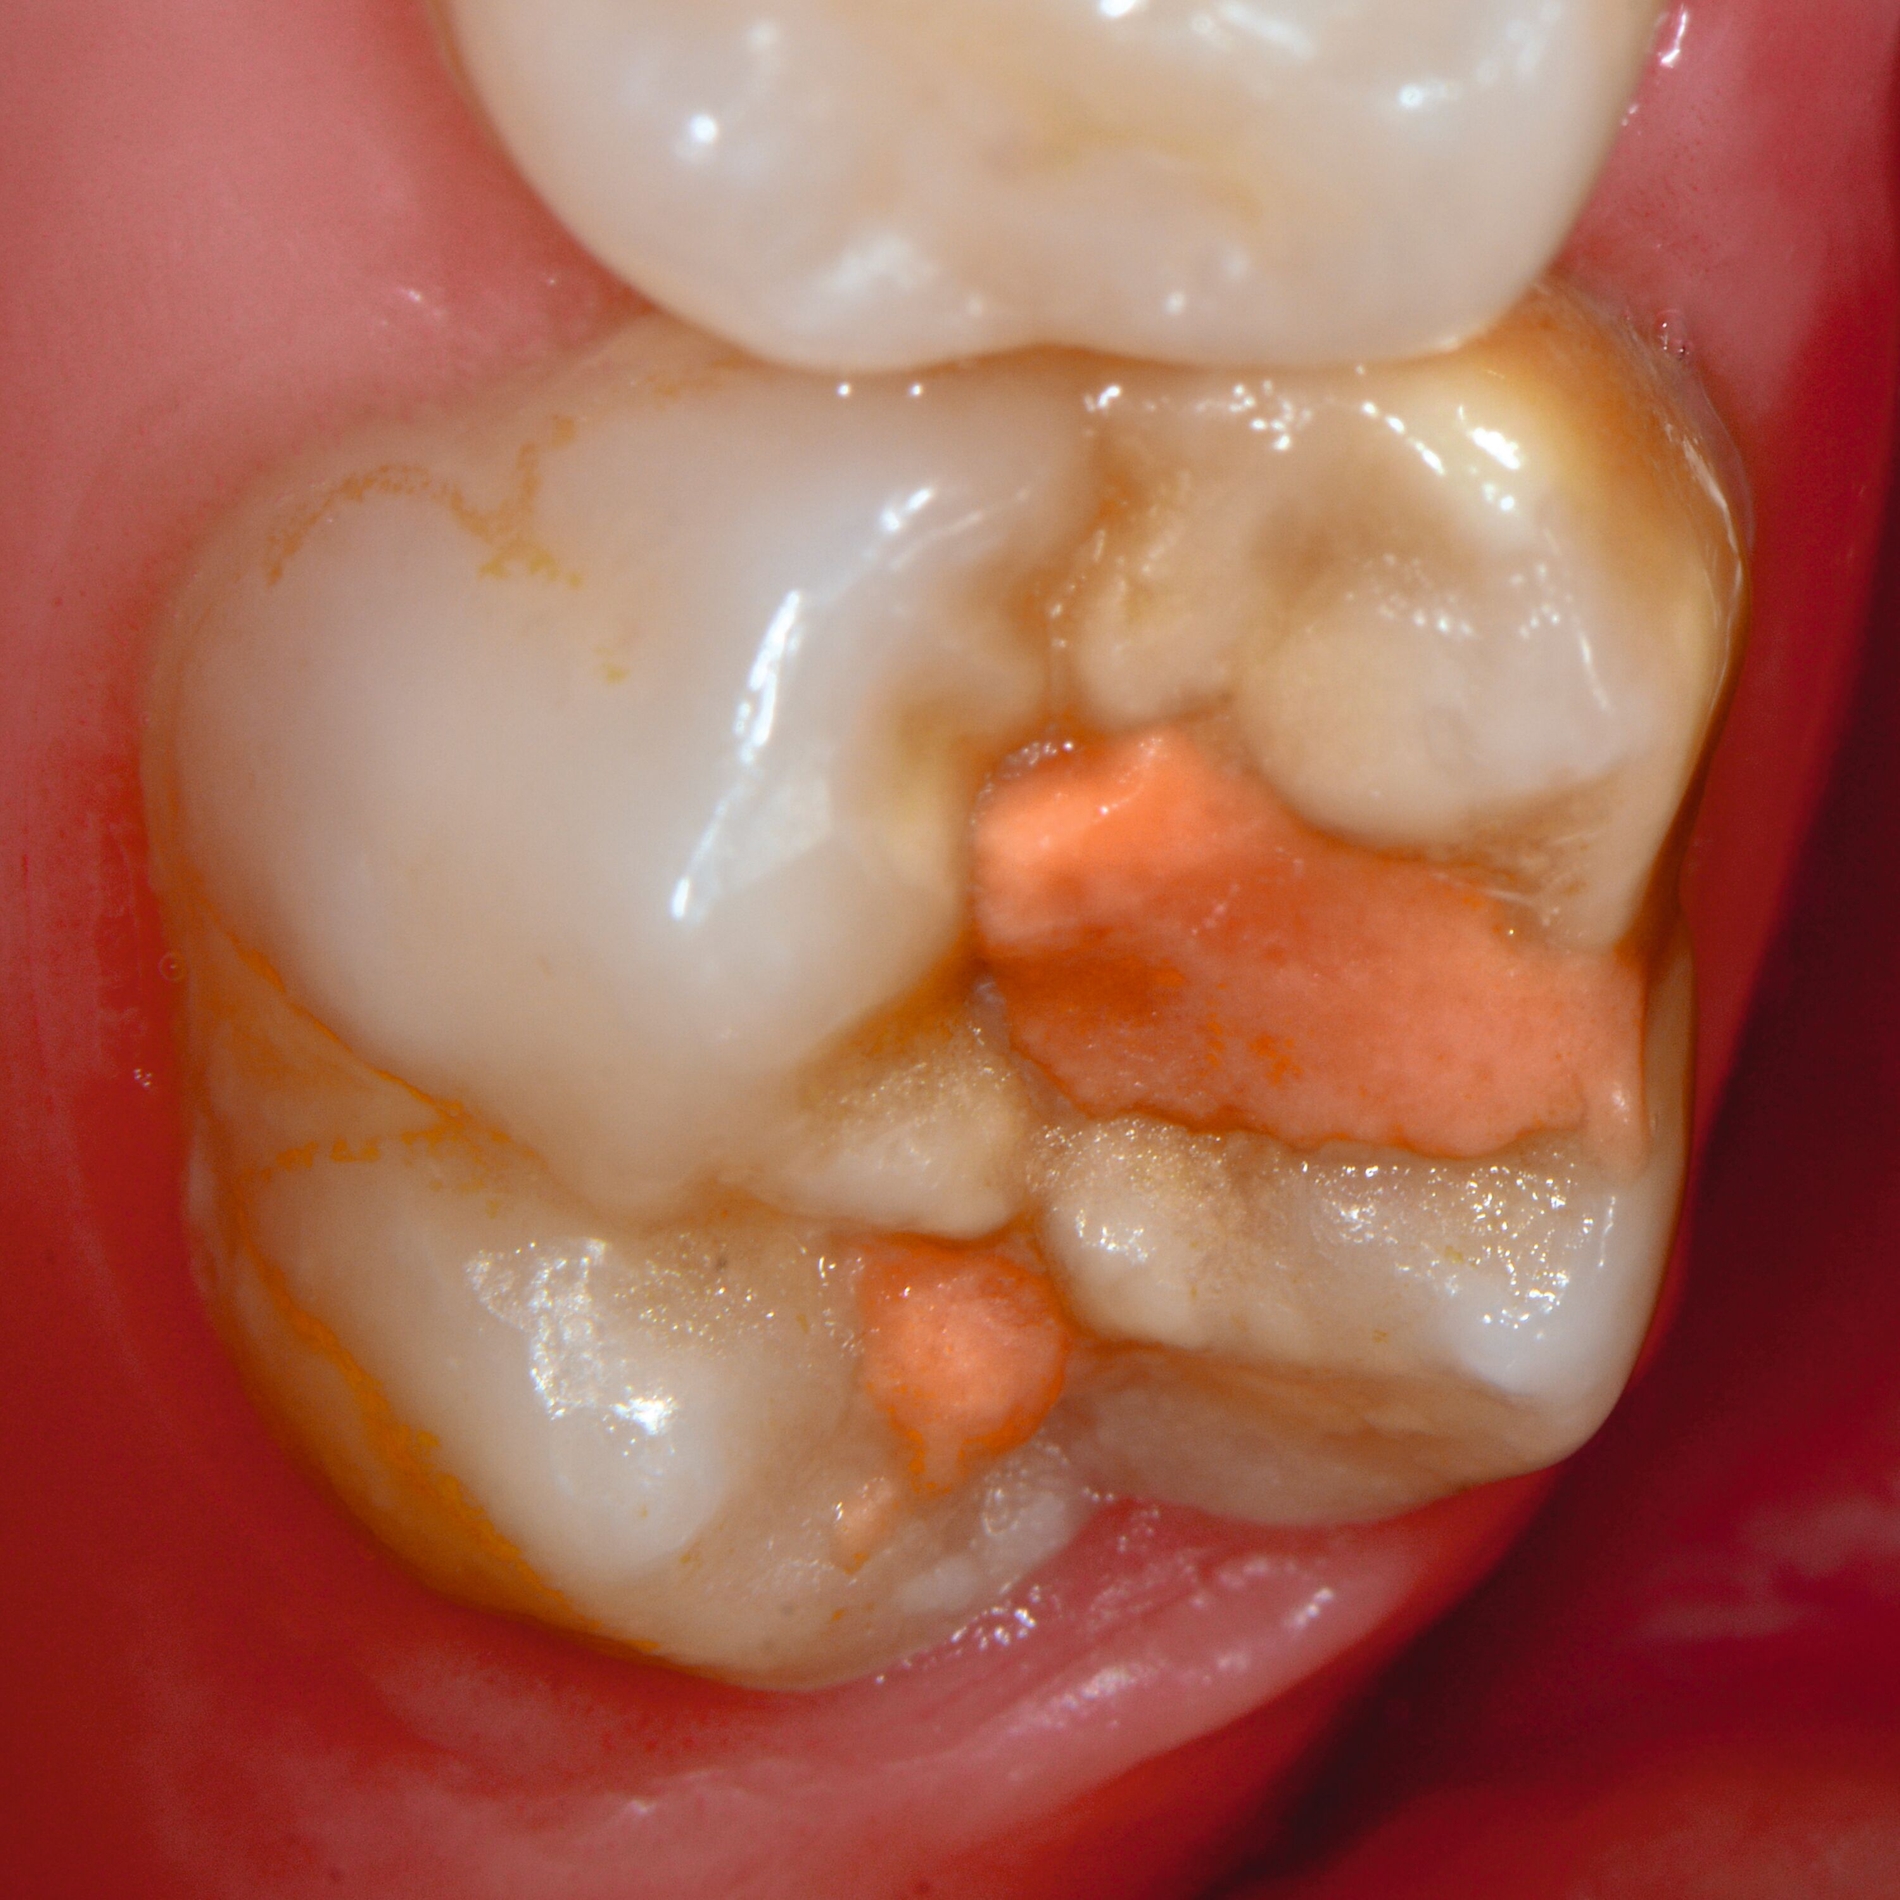

Das klinische Erscheinungsbild an bleibenden Zähnen zeigt typischerweise weißlich-gelbe bis gelblich-braune Opazitäten, die zumindest in einigen Bereichen durch eine scharfe Abgrenzung (engl.:„demarcated opacities“) zum gesunden Zahnschmelz charakterisiert sind (Abbildungen 3 und 4). Die abgegrenzten Hypomineralisationen befinden sich mehrheitlich im Bereich der inzisalen Kronenhälfte unabhängig von dem Auftreten an Front- oder Seitenzähnen. Die Ausprägung am Zahn kann dabei auf einzelne Areale oder Höcker begrenzt sein.

An umfangreich hypomineralisierten Zähnen können Schmelzeinbrüche (engl.: „enamel breakdown“ oder „enamel desintegration“, Abbildung 5) auftreten [Lygidakis et al., 2010; 2022]. Da diese oftmals die Folge einer fehlenden Belastungsfähigkeit des Zahnschmelzes sind und erst nach der Einstellung der Zähne in die Okklusion auftreten, werden sie auch als posteruptive Schmelzeinbrüche bezeichnet. Sie sind häufig im Bereich der Kauflächen beziehungsweise Höcker der Molaren zu finden, führen zur Dentinexposition und damit einhergehend zu ausgeprägten Hypersensitiven insbesondere bei Kindern, deren Zähne gerade erst durchgebrochen sind [Linner et al., 2021].

Bei post- beziehungsweise präeruptiven Oberflächendefekten ergibt sich in einigen Fällen die Indikation zur Restauration dieser MIH-Zähne. Unter Verweis auf die Lokalisation von MIH-bedingten Hypomineralisationen außerhalb der typischen Kariesprädilektionsstellen – zum Beispiel okklusale Fissuren und Grübchen oder Approximalflächen – werden diese als „atypische Restaurationen“ (engl.: „atypical restoration“, Abbildung 6) klassifiziert. Als ein weiteres Erkennungsmerkmal gilt die Präsenz von Hypomineralisationen im Bereich der Restaurationsränder. MIH- und kariesbedingte Restaurationen können und sollten sicher voneinander abgegrenzt werden.

Für die Dokumentation und Klassifikation der MIH wurden verschiedene Systeme vorgeschlagen. Als historisch und veraltet gilt der (modifizierte) DDE-Index. Demgegenüber haben die Kriterien der EAPD – abgegrenzte Opazitäten (Abbildung 3 und 4), Schmelzeinbrüche (Abbildung 5), atypische Restaurationen (Abbildung 6) – mittlerweile die weiteste Verbreitung gefunden. Diese wurden 2003 erstmals zur Beschreibung der MIH auf empirischer Basis publiziert [Weerheijm et al., 2003] und den Jahren 2010 und 2022 im Rahmen der damaligen MIH-Workshops bestätigt [Lygidakis et al., 2010; 2022].